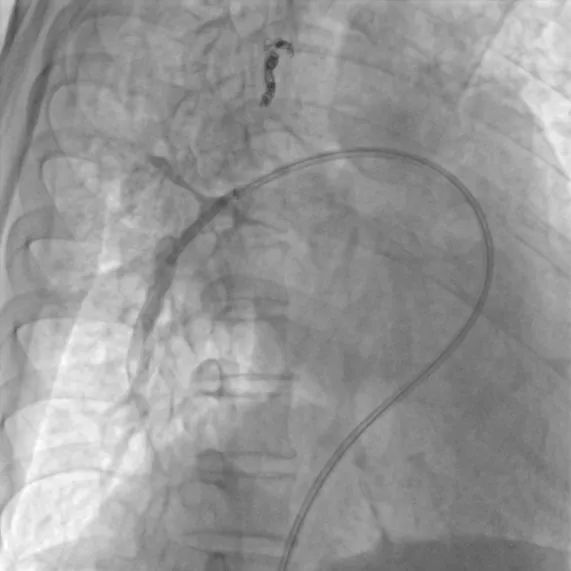

第四次(2021.7)拟行肺动脉支架植入术入院,于2021-7-7行右心导管检查+肺动脉造影+肺动脉支架植入术:支架植入前测量右房压为25/9(15)mmHg,右心室压为55/2(19)mmHg,肺动脉压为55/29(38)mmHg,CO 2.2 L/min,PVR 11.8WU。测量左肺下叶肺动脉近端压力51/23(32)mmHg,远端压力为15/11(12)mmHg,右肺下叶肺动脉近端压力52/20(31)mmHg,远端压力为11/8(9)mmHg,于右肺动脉基底干狭窄处植入PLU-STENT M30支架一枚,测量病变远端压力为51/23(32)mmHg,未见明显压差。

肺动脉支架植入术